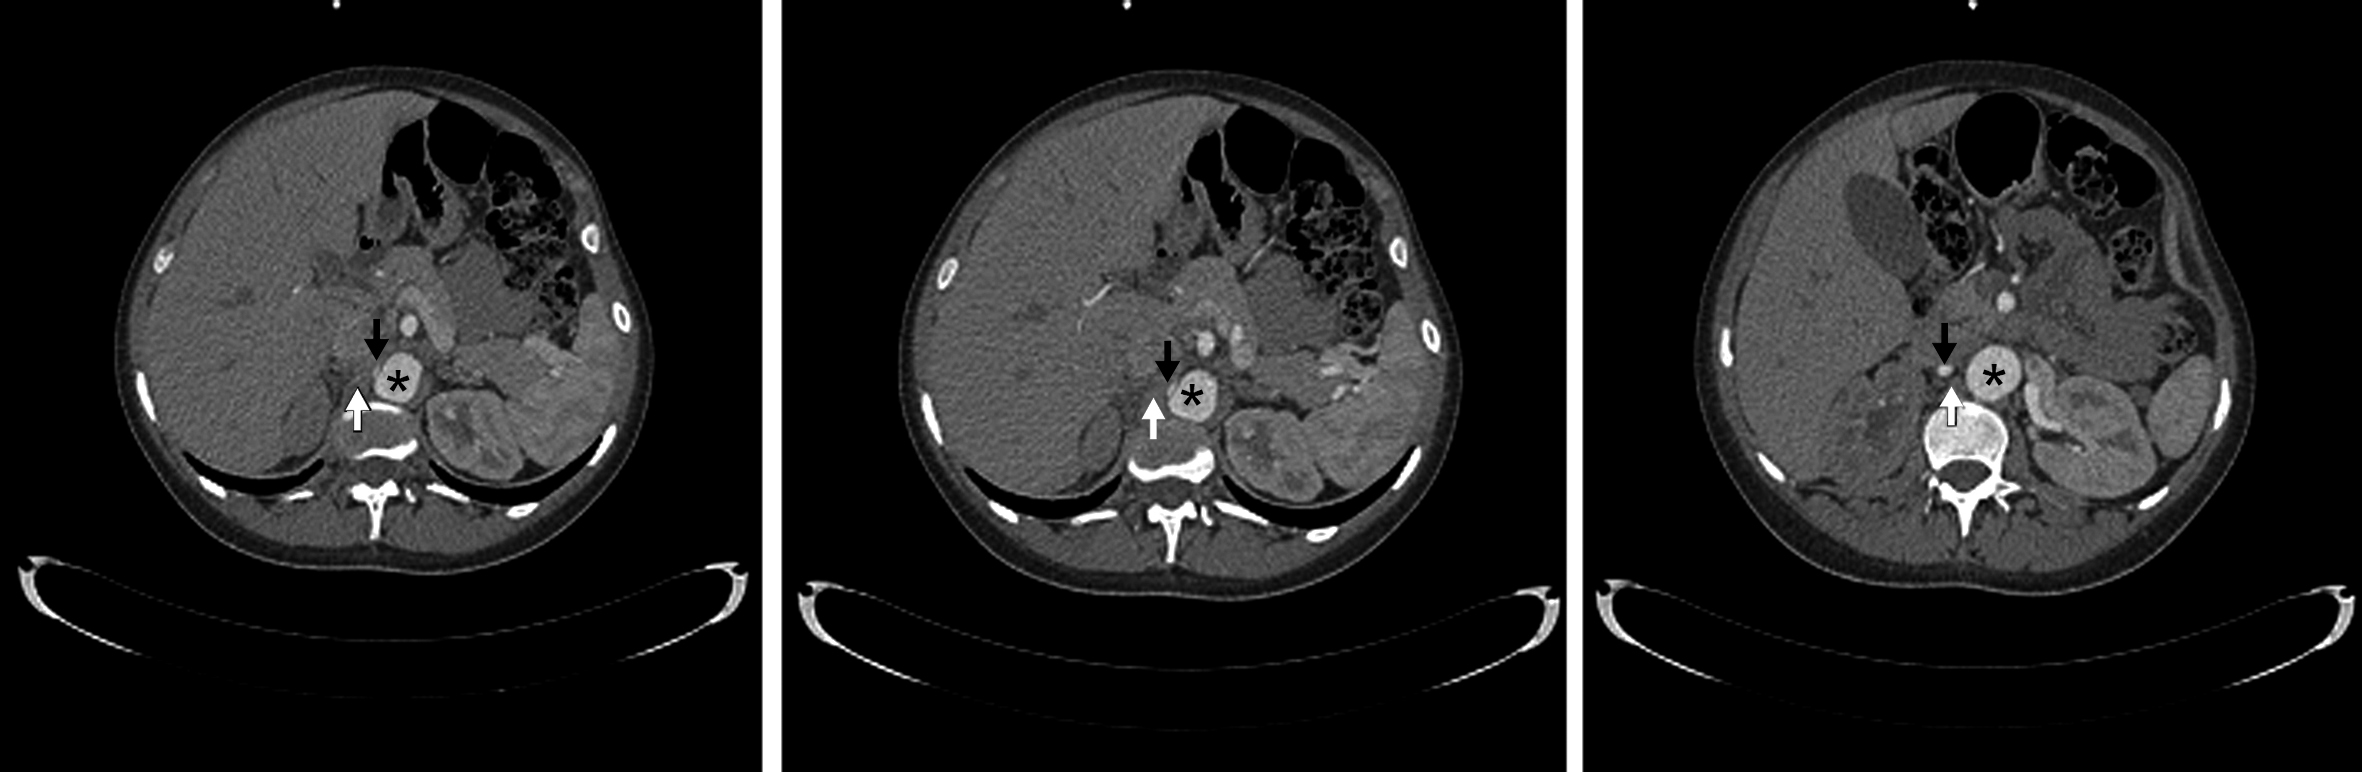

La arteria renal derecha es única, se encuentra permeable, y presenta franca disminución de su calibre y trayecto “verticalizado” en su sector proximal, transcurriendo entre la aorta abdominal y la crura diafragmática ipsilateral en su segmento inicial. Distalmente la arteria renal derecha presenta calibre normal, de aprox. 6 mm de diámetro. Así mismo se observa realce asimétrico de ambos riñones tras la administración de medio de contraste i/v, evidenciándose menor captación del mismo en forma difusa a derecha (nefrograma tardío) en comparación con el riñón contralateral, lo cual traduce hipoperfusión renal. (Figs. 1 y 2)

El tronco celíaco y la arteria mesentérica superior se encuentran permeables y de calibre habitual. Se identifica un origen alto de las ramas viscerales de la aorta abdominal, a saber, el tronco celíaco a la altura del espacio discal T11-T12, la arteria mesentérica superior a nivel del cuerpo vertebral de T12, la arteria renal derecha a nivel del espacio T12-L1 y de la arteria renal izquierda a nivel del margen superior de cuerpo de L1. (Fig. 3)

Por último destacamos la presencia de un útero grávido con feto en su interior, antecedente que ya conocíamos. Los hallazgos descritos son compatibles con el planteo de Síndrome de atrapamiento de la arteria renal derecha por la crura diafragmática.

Figura 1

Angiografía de Aorta por TC Cortes axiales. (*) Aorta abdominal, (flecha blanca) Crura diafragmática derecha, (flecha negra) Arteria renal derecha.